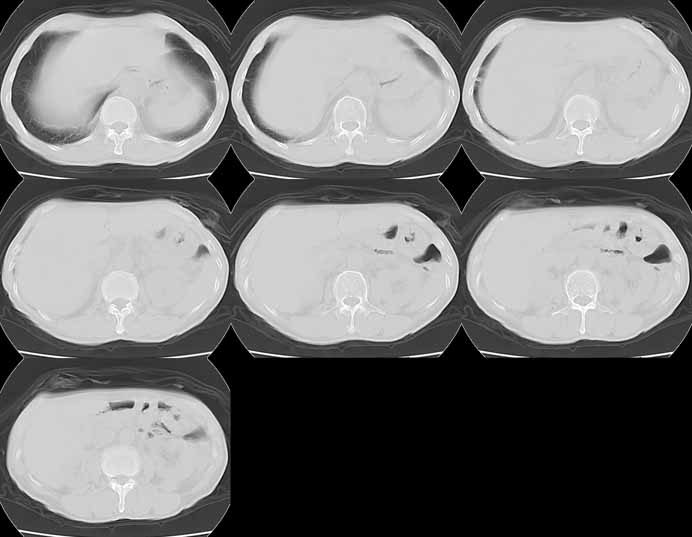

Lung Cancer: Adenocarcinoma:"High-speed screening mode."

8mmx4, Pitch 6, 384mm, 4-seconds, 150-mAs: